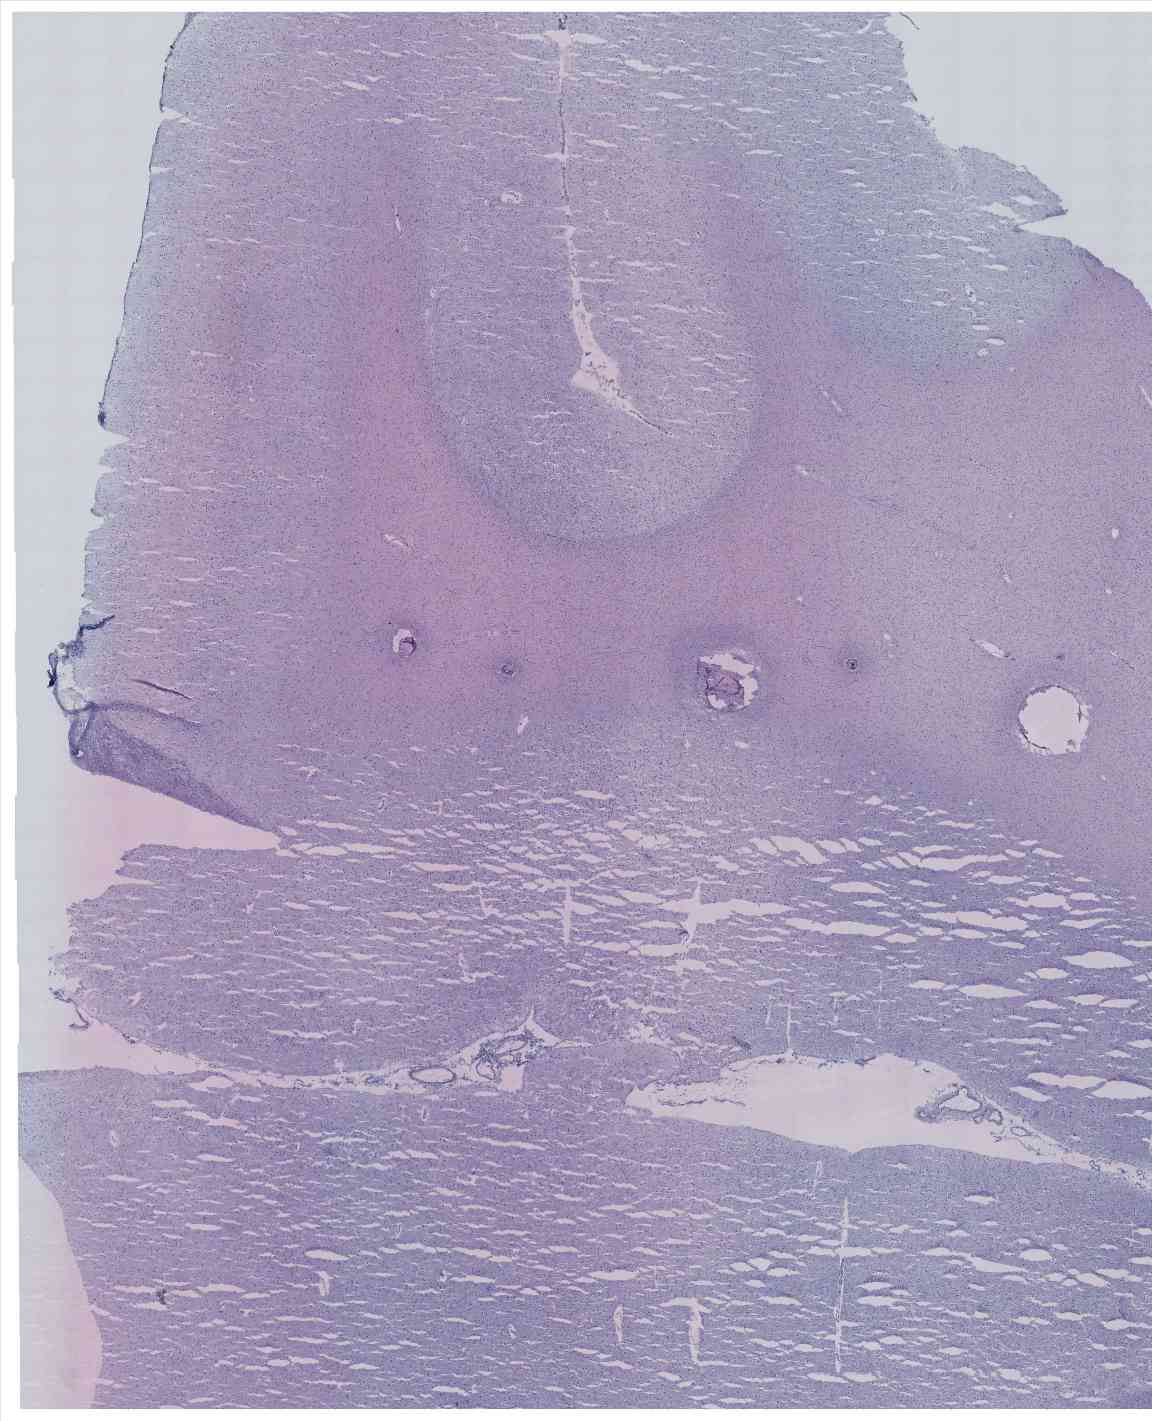

Chip 052 Well D1